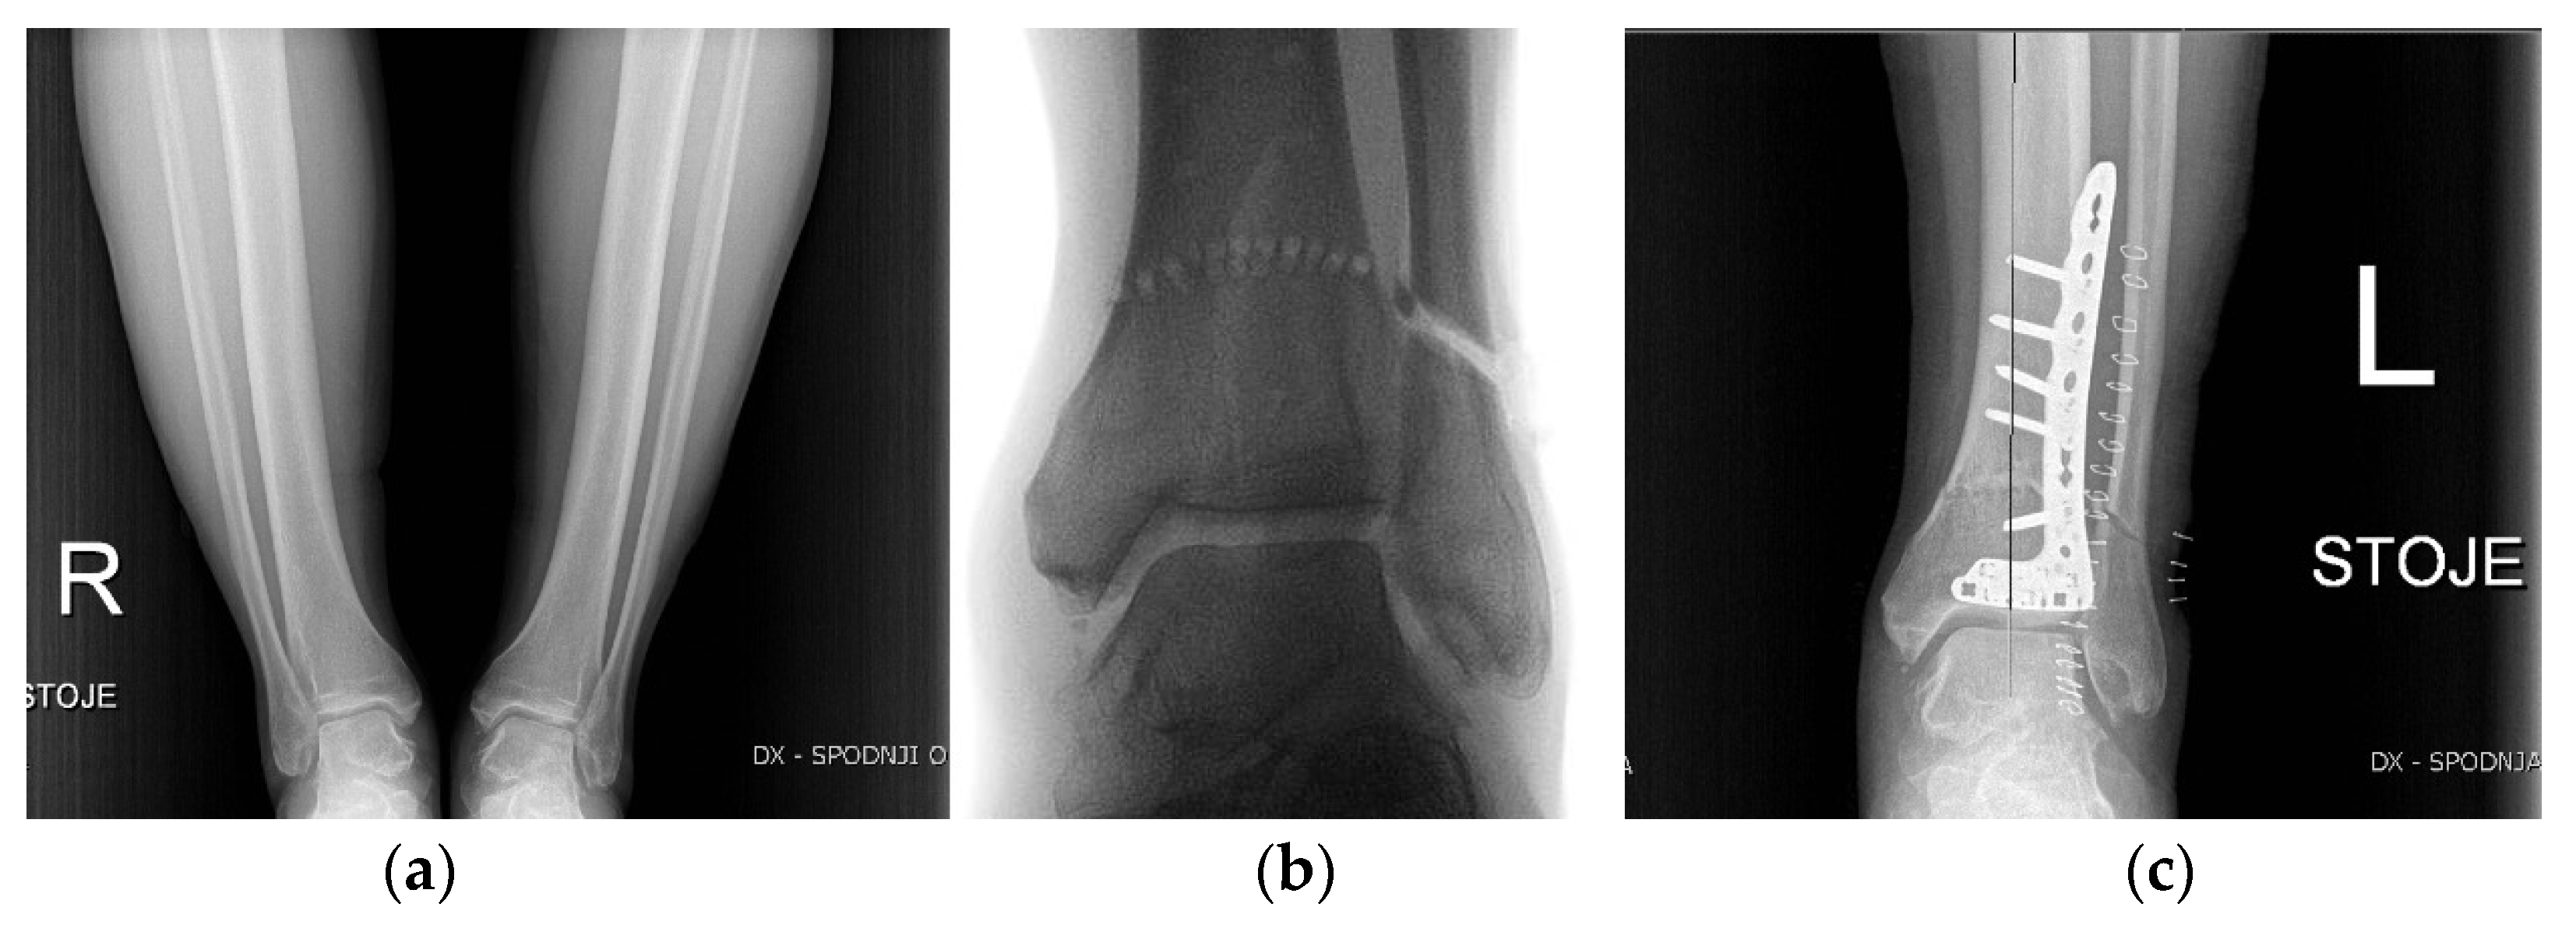

3.7. Ankle and Foot

- Valderrabano, V.; Horisberger, M.; Russell, I.; Dougall, H.; Hintermann, B. Etiology of Ankle Osteoarthritis. Clin. Orthop. 2009, 467, 1800–1806. [Google Scholar] [CrossRef] [PubMed]

- Chopra, V.; Stone, P.; Ng, A. Supramalleolar Osteotomies. Clin. Podiatr. Med. Surg. 2017, 34, 445–460. [Google Scholar] [CrossRef] [PubMed]

- Colin, F. Tibia Dome-Shaped Osteotomy for a Valgus Deformity in a Ball-AndSocket Ankle Joint: A Case Report. Clin. Res. Foot Ankle 2013, 1, 116. [Google Scholar] [CrossRef]

- Zhao, H.; Liang, X.; Li, Y.; Yu, G.; Niu, W.; Zhang, Y. The Role of Fibular for Supramalleolar Osteotomy in Treatment of Varus Ankle Arthritis: A Biomechanical and Clinical Study. J. Orthop. Surg. 2016, 11, 127. [Google Scholar] [CrossRef]